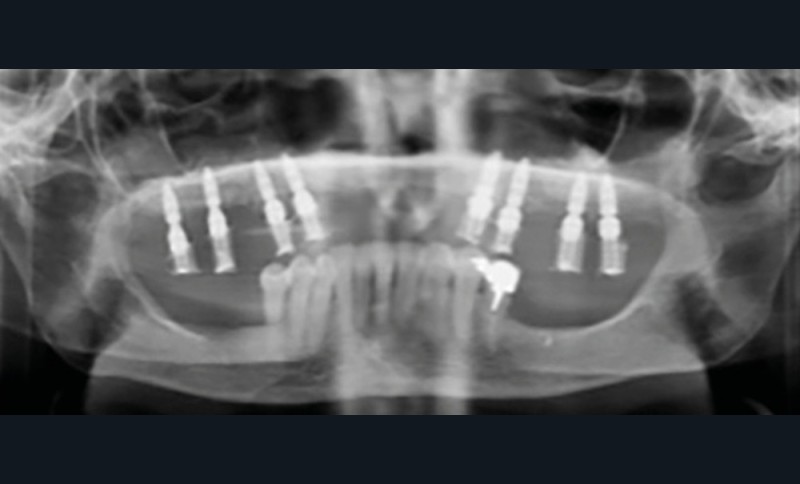

Le matching classique avec les fichiers STL et Dicom fut imprécis. La technique inspirée du « double scan » à l’aide de points radio-opaques sur la PAP provisoire maxillaire et d’un double CBCT a permis d’obtenir un matching extrêmement précis et la conception d’un projet prothétique numérique (Nemotec) associé à un Smile design (fig. 2). La modélisation 3D et le CBCT ont permis d’élaborer une planification implantaire, des guides à étages et un bridge complet provisoire en PMMA usiné (Biotech). La planification de 8 implants au niveau des 7/6/4/3 en fonction du volume osseux disponible et du projet prothétique virtuel a confirmé la possibilité de proposer un traitement sans greffe antérieure (fig. 3).